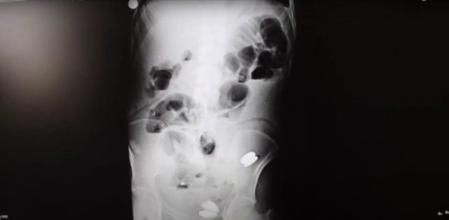

Para su sorpresa, los sanitarios de Ipekyolu, Turquía, encontraron nada más y nada menos que 233 objetos en el interior de su estómago. ¿Cómo han podido llegar hasta allí? ¿Cómo ha podido sobrevivir con una cantidad tan inmensa de objetos en su interior? Se preguntaban los médicos.

Entre los 233 elementos descubiertos en su estómago había: monedas, clavos, pilas, fragmentos de vidrio, imanes, piedras y tornillos. Una serie de objetos peligrosos que descolocó completamente a los sanitarios que no se explicaban cómo había podido suceder y más aún tratándose de un adulto.

Aunque los sanitarios optaron por un ultrasonido endoscópico (EUS), que combina la endoscopia y el ultrasonido, y una serie de radiografías, cuando vieron todo lo que tenía dentro rápidamente lo llevaron a quirófano de urgencia para someterle a una intervención y extraer todos los objetos.